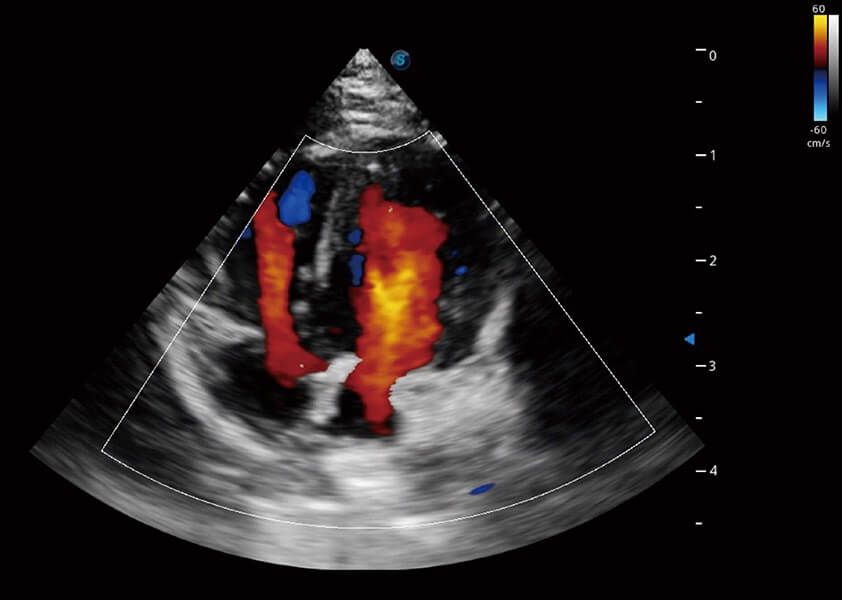

ProPet 60 作为一款高端台式动物超声设备,为动物医生的日常诊断提供了一系列贴合动物临床需求、解决临床实际问题的高级成像功能。凭借全系列高清探头,满足医生对腹部、心脏、生殖、浅表、肌骨等成像的所有需求,切实帮助您提升检查效率,提高诊断信心。

动物是人类最亲密的朋友和最值得信赖的伙伴。16877太阳集团也一直致力于探索动物专用的超声影像解决方案。 全新推出的ProPet系列,是16877太阳集团在动物超声影像智能化、专业化、精准化的一次跨越式革新。动物不能用言语来表述自己的不适,通过超声影像,ProPet系列搭建了动物医生与不同物种沟通的“桥梁”,为动物医生注入了“治愈之力”。